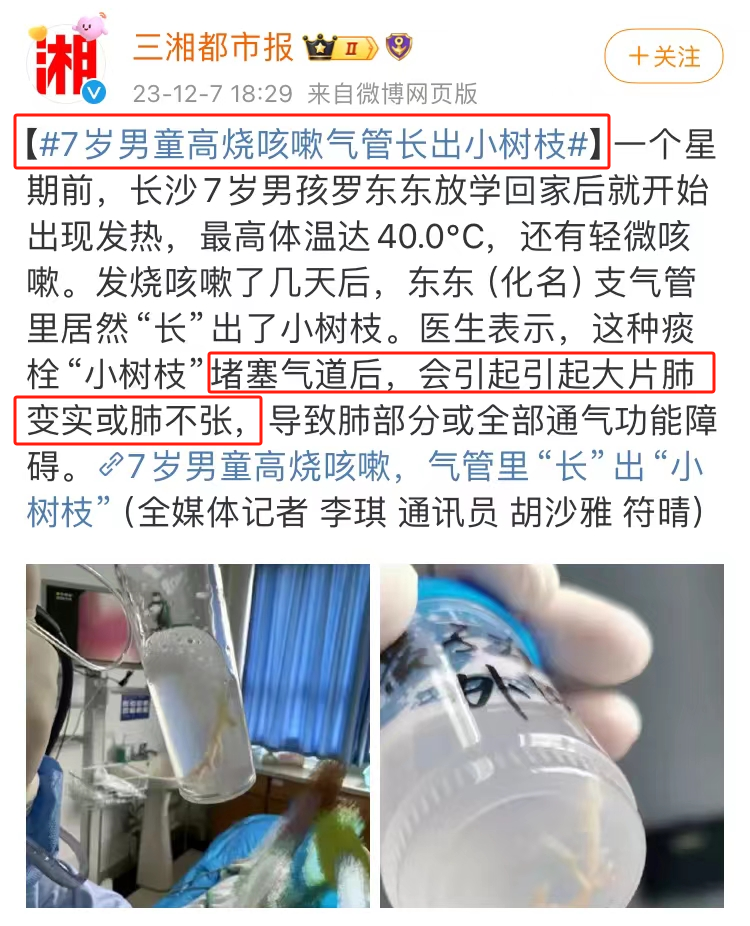

男孩高烧咳嗽后↓形成痰栓↓

男孩高烧咳嗽后↓形成痰栓↓